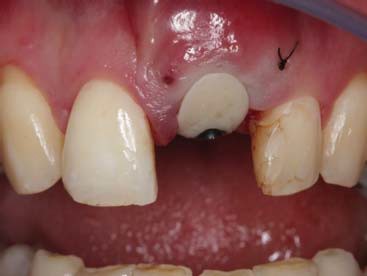

Finalizado toda a parte cirúrgica foi feito o posicionamento de um cilindro provisório e da tampa de cobertura que havia sido confeccionado no gesso e feita a união com resina tipo flow, seguindo do acabamento e polimento fora da boca. Uma vez pronto o cicatrizador personalizado, este foi instalado com o torque de 15N e uma prótese parcial removível provisória foi instalada (figura 9, figura 10, figura 11, figura 12, figura 13 e figura 14).

A paciente retornou após 4 meses e foi constatado um resultado satisfatório da cicatrização tecidual e a manutenção da arquitetura gengival (figura 15 e figura 16).